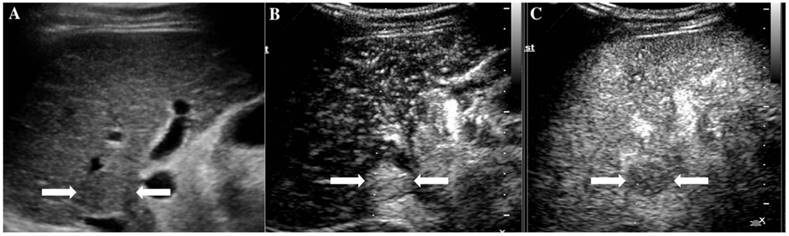

At last, of the 37 observations classified as LR-5, 33 (89.19%) were pathologically confirmed as malignant including 1 ICC (2.7%) and 32 HCC (86.49%). The typical ultrasound images are shown in Figure 1. However, 4 lesions (10.81 %) were histologically proved to be benign, 3 regenerative nodule (8.11%) (Figure 2) and 1 focal nodular hyperplasia (2.7%). With respect to the 8 LR-4 observations, 4 cases (50%) turned out to be HCCs (Figure 3). Angioma, focal nodular hyperplasia (Figure 4) and regenerative nodule accounts for 12.5% (1/8), 12.5% (1/8) and 25% (2/8) respectively. Nine observations categorized as LR-M consist of 7 (77.78%) HCC (Figure 5), 1 (11.11%) ICC and 1 (11.11%) RLH, based on pathological findings. The correct diagnoses of HCC, ICC and benign lesions were used to measure diagnostic accuracy for LI-RADS-CEUS. An example of successful categorization of HCC as LR-3 was shown in Figure 6. For the diagnosis of HCC, the overall diagnostic accuracy of LR-5 was 86.49 % (32/37) and that of LR-4 was 50% (4/8). However, the diagnostic accuracy of LR-M was only 11.11% in the retrospective study (Table 3).

Figure 3

The assigned LI-RADS category of this patient was LR-4. Hepatocellular carcinoma (HCC) was confirmed by histopathology. A. Conventional ultrasound displayed a hypoechoic nodule (arrows) of about 1.7cm on the left hepatic lobe of a 57-year-old male patient. B. CEUS showed hyperenhancement (arrows) in arterial phase. C. CEUS showed isoenhancement (arrows) in the late phase.

Figure 4

It illustrates an example of misinterpretation with LI-RADS-CEUS (LR-4). The ultimate pathological diagnosis was focal nodular hyperplasia (FNH). A. Conventional B-mode image showed a 1.4cm isoechoic nodule (arrows) on the left hepatic lobe of a 48-year-old male. B. CEUS displayed hyperenhancement (arrows) during the arterial phase. C. CEUS showed isoenhancement (arrows) during the late phase.